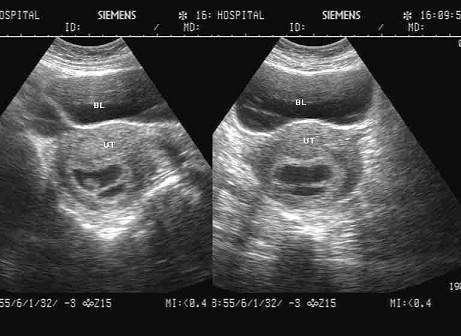

问题 女,23岁,停经45天,阴道无异常分泌物,子宫附件声像图如下,图中所示为?(?)

选项 A.正常早孕孕囊及胚外体腔 B.双胎妊娠双孕囊 C.难免流产 D.子宫肌瘤 E.早孕并宫腔积液

答案 A